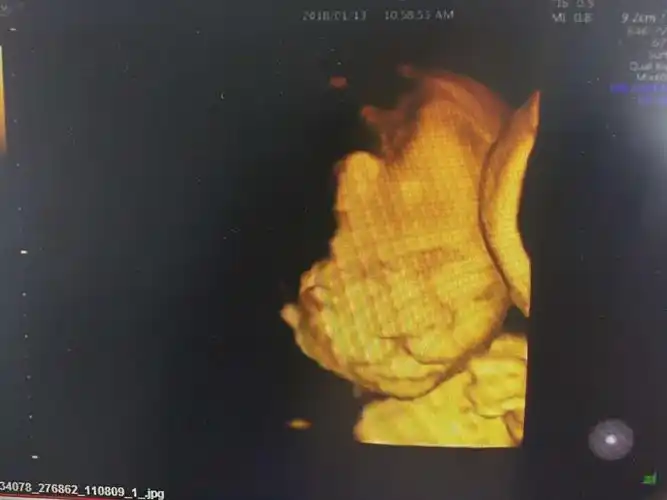

其它 扎赉特旗妇幼保健院彩超室 "gee8"四维彩超的引进,在妇产科领域

聪明的唇腭裂胎儿,为了出生拍四维彩超时用手挡住嘴巴,不让人看见!

请帮忙看下四维彩超,是兔唇吗?很是担心!

前两天做的四维,四维图上看起来正常,可是放大的照片看起来像兔唇,问

请各位宝妈帮我看一下这个四维是兔唇吗?